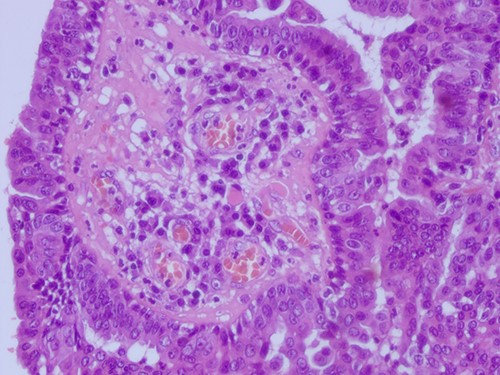

The histopathological examination found cystic invaginations of the infundibular epithelium projecting into the dermis, covered by a double cell layer (Fig. 2), proliferation of glands with prominent papillary architecture (Fig. 3) and fibrous cores containing numerous stromal plasma cells (Fig. 4). Other findings include verrucous (papillomatous) epidermal hyperplasia with hyperkeratosis and hypergranulosis (Fig. 5), irregular duct-like structures and cystic spaces (Fig. 6) and glands with double layer of cuboidal columnar epithelium and numerous stromal plasma cells (Fig. 7). These findings are compatible with Syringocystadenoma papilliferum with no signs of malignancy.

H&E staining 40× magnification Glands with double layer of cuboidal columnar epithelium and numerous stromal plasma cells.